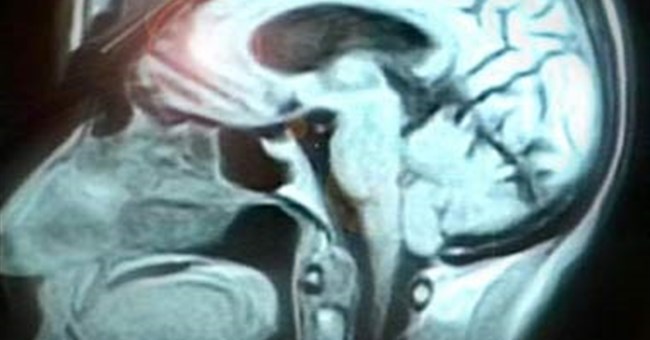

• Não chú ý theo hai cách

Não chú ý theo hai cách